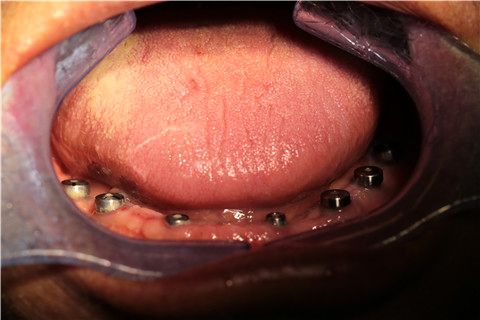

下半口植入7颗种植体

上半口植入3颗种植体